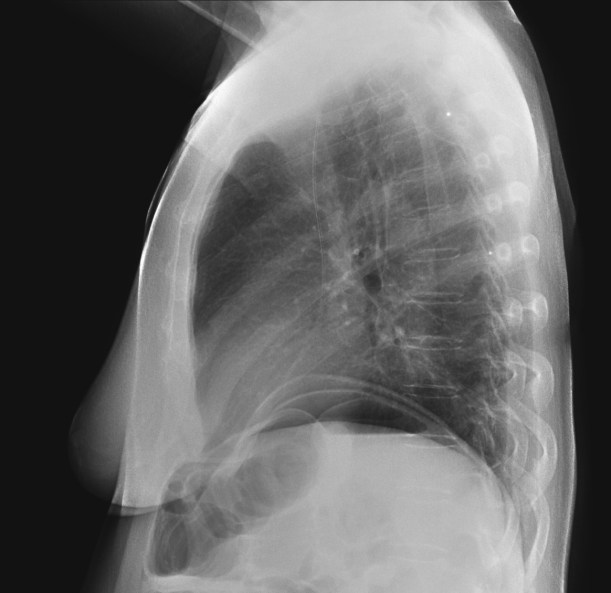

CASO: Febrícula y tos de 4 días de evolución.

Hallazgos:

- En la placa PA se observa una asimetría en los hilios pulmonares, el hilio izquierdo tiene una densidad aumentada.

- Tras examinar la placa lateral se observa un aumento de densidad en la columna que puede ser compatible con una condensación, es el signo de la desnificación vertebral.

SIGNO DE LA DENSIFICACIÓN VERTEBRAL: En la radiografía lateral normal, la densidad de la columna torácica tiende a disminuir desde la parte superior hasta el diafragma; la alteración de ese patrón por la presencia de una densidad superpuesta a la columna, indica la existencia de una consolidación pulmonar. Este signo adquiere especial valor cuando en la proyección posteroanterior la consolidación está oculta en el espacio retrocardíaco o en la base pulmonar.